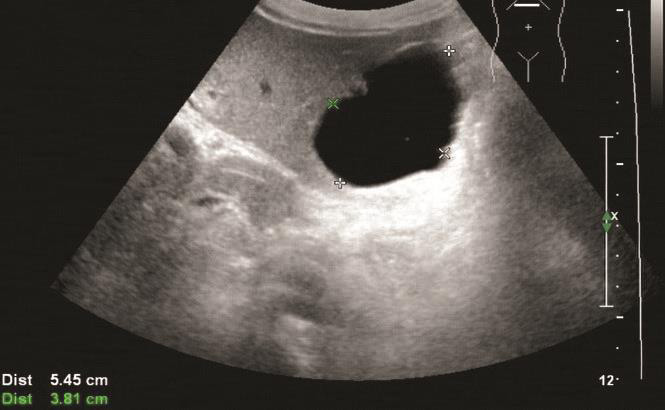

(1)典型肝囊肿,呈边界清晰的圆形或椭圆形,囊壁薄而清晰,内部均匀无回声,后方回声增强,可伴侧方声影,囊壁无彩色血流信号(图1-9-1、图1-9-2)。

图1-9-2 肝内多发囊肿灰阶超声图像